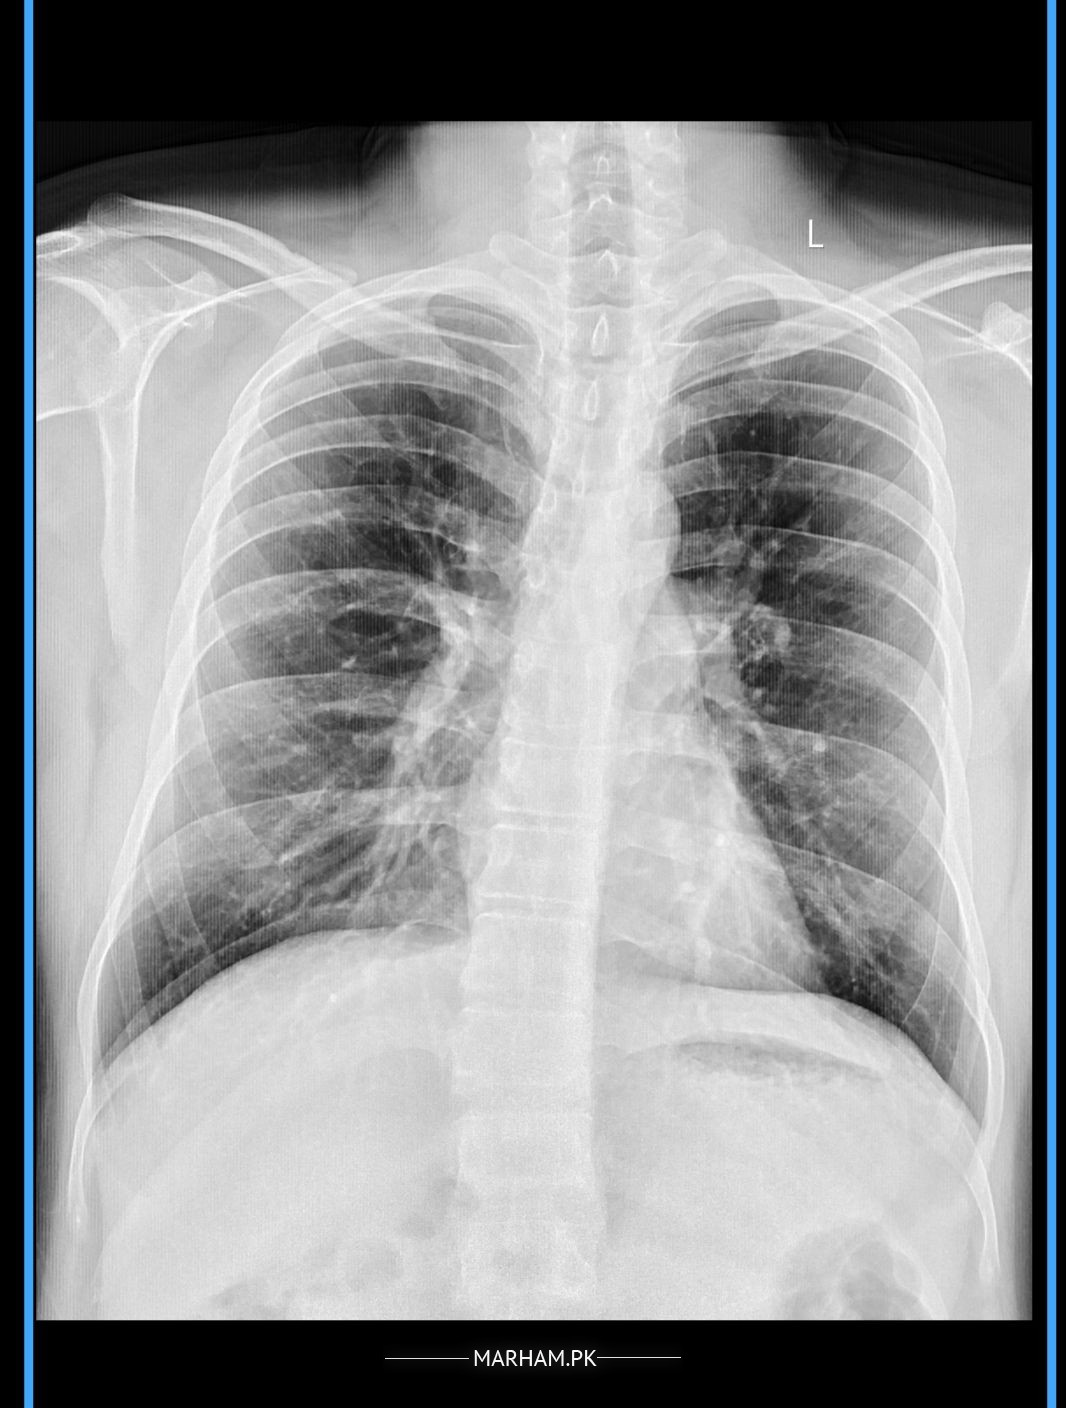

Kindly see attached my chest x-ray and give opinion is there any spots/scarring on chest, I have to do Qatar overseas employment medical test, in that test they don't pass if they found any chest scarring.

I never have/had TB, never smoking but I have mild asthma.

Looks normal

Your xray is normal just prominent bronchovascular (lung) markings

normal X ray.

Aoa.. yes it has previous non homogenous opacities scaring plus haziness.

You need to get your HRCT chest done.

Plus how long have you taken anti tuberculous drugs? And what inhaler are you using now a days? Get your spirometry done also.

Your asthma should be controlled with proper inhalers and medicines. Rest the old healed scars cannot be removed but you should avoid getting it worse due to fibrosis.

Aoa .Its normal chest xray

Aoa.Your Chest Xray is clear.....the white fots seen in the middle are end-on bronchi...they are normal.